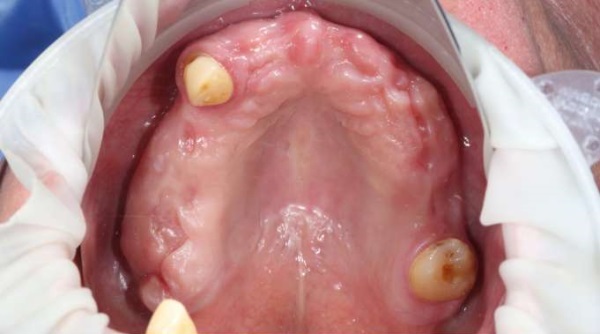

Осмотр полости рта: на верхней челюсти визуализируется частично-съемный протез на кламмерах с опорой на зубы 1.3 и 2.7. Наддесневые и поддесневые зубные отложения отсутствуют, слизистая оболочка бледно-розового цвета, умеренно увлажнена, кровоточивость при зондировании отсутствует. Глубина зондирования в области всех зубов не превышает 4 мм. Наблюдается удовлетворительное состояние тканей пародонта, без признаков воспаления (рис. 2).

Рис. 2. Состояние мягких тканей полости рта пациента А. на момент обращения

Примечание: фотография выполнена авторами

Fig. 2. Soft oral tissue in patient A. at the time of consultation

Note: The photograph was taken by the authors.